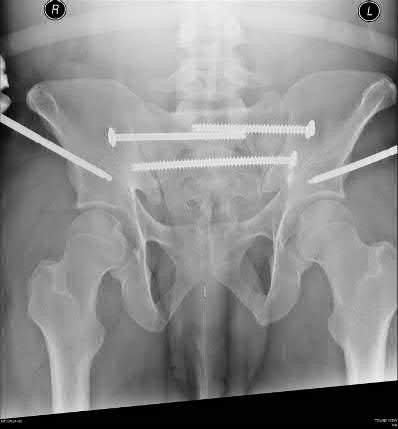

A 44-year-old male presents after being struck by a car. He is hypotensive, and has an obvious open tibia and a closed femoral shaft fracture. A pelvic radiograph is obtained and shown in Figure A. A representative CT scan image in shown in Figure B. The patient is placed in a pelvic binder, and his blood pressure normalizes with crystalloid and a blood transfusion. He then undergoes pelvic angiography, and his internal iliac artery is embolized. Which of the following definitive treatment options is most appropriate in this case?

The radiographs and CT scan show a fracture pattern consistent with an APC-III injury. This is most appropriately treated with pubic symphysis ORIF with a multi-hole plate and posterior iliosacral screw fixation.

APC-III pelvic ring injuries are associated with with disruption of the anterior and posterior SI ligaments (SI dislocation) as well as disruption of

sacrospinous and sacrotuberous ligaments. They are commonly associated with vascular injury and retroperitoneal bleeding.

Sagi et al studied the radiographic and clinical outcome of symphyseal plating techniques, specifically comparing two hole (THP) vs multi-hole plating (MHP). Retrospective review of charts and radiographs immediately after the index procedure to latest follow-up was performed. When comparing the 2 different methods of anterior fixation, they found that the rate of fixation failure was greater in group THP (33%) than group MHP (12%). When evaluating the presence of a malunion as a result of these 2 treatment methods, there were more present in the THP group (57%) than in the MHP group (15%). On the basis of these findings, the authors recommended multi-hole plating of unstable pubic symphyseal disruptions.

Grimshaw et al performed a biomechanical study to determine the failure risk and potential benefit to use of locked fixation constructs in simulated pelvic ring injuries. The authors used a six-hole 3.5-mm plate specifically designed for the symphysis pubis with the capability of fixation in locked or unlocked mode, six pelves were fixed with locked screws and six pelves were fixed standard unlocked bicortical screws. Biomechanical testing was performed, and no abrupt failures were noted. However, locked plating of the pubic symphysis did not appear to offer any advantage over the standard unlocked technique

Illustrations A, B, and C show the AP, outlet, and inlet postoperative radiographs.